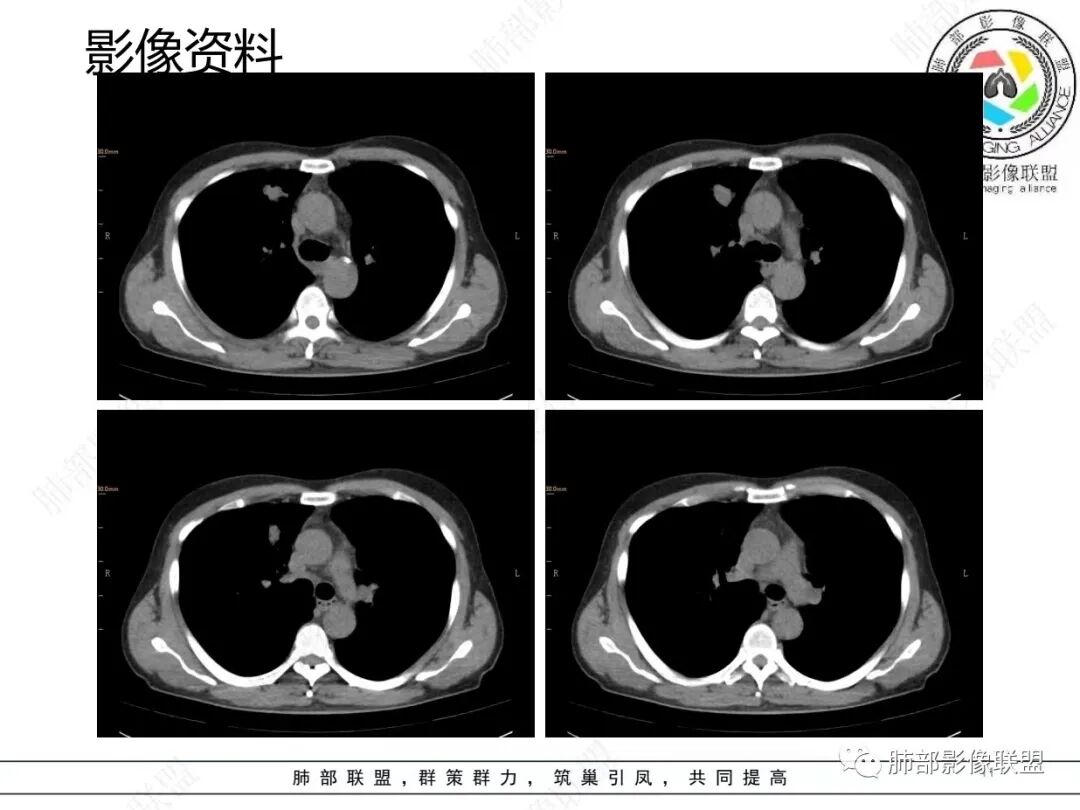

1.临床特点:52岁男性,体检发现肺结节。有吸烟史。非小细胞肺癌相关抗原与神经元烯醇化酶轻度升高。2.影像特点:右肺上叶前段可见不规则结节影,整体膨隆,可见浅分叶,周围局部可见边界清楚的磨玻璃影。可见血管集束征及脐凹征,临近叶间胸膜受牵拉凹陷,局部支气管到达病灶边缘后显示截断。3.病例小结:中老年吸烟男性,右肺上叶前段不规则结节,膨胀感较明显,收缩力强,支气管截断,加上边界清楚的磨玻璃影。符合浸润性腺癌表现。

4.相关知识:浸润性肺腺癌分为:附壁状、腺泡状、乳头状、微乳头状、实体型,较少见的生长模式包括浸润性黏液型、胶样、肠型和胎儿型。腺癌影像表现为磨玻璃影、部分实性结节、实性结节或实变。